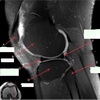

Perfectly

11

Q

What is letter A?

A

ANTERIOR LABRUM